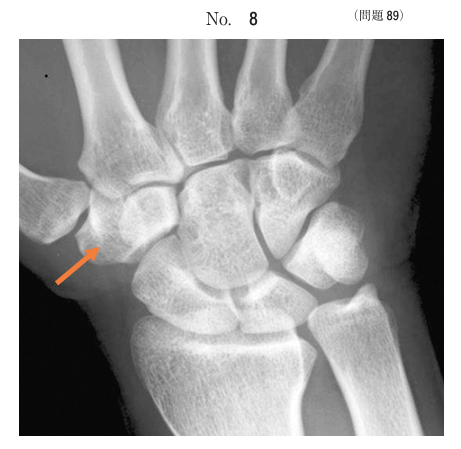

午前/問題89

手根骨の正面X線写真別冊No. 8 を別に示す。矢印で示すのはどれか。

1.舟状骨

2.月状骨

3.有頭骨

4.有鉤骨

5.大菱形骨